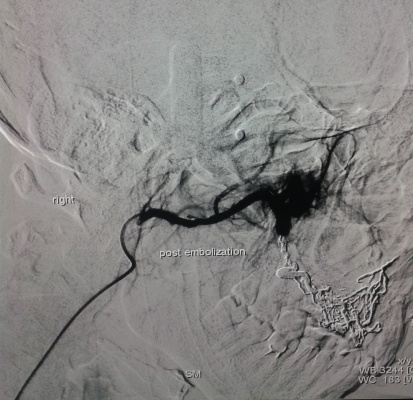

S-a utilizat procedura minim-invazivă endovasculară, care constă în cateterizarea supraselectivă a aferentelor arteriale a malformaţiei, cu embolizarea ulterioară a acestora pîna la stoparea fluxului de sînge prin malformaţie. De obicei, o astfel de procedură durează de la 40 minute pînă la două ore. Extrem de rar pot apărea complicaţii de ordin local (hematom, tromboză, fistulă) sau la nivelul regiunii malformaţiei (ulceraţie a mucoasei cu hemoragie, embolizarea ţesutului nedorit cu necroze). Scopul intervenţiei a fost de a micşora volumul malformaţiei (cu lichidarea ei în varianta ideală), dar şi de a atribui un aspect estetic. Astfel de proceduri pot fi asociate cu metode chirurgicale reconstructive de excizie a malformaţiei sau sclerozare, în cazuri selecte, care pot produce deformaţiuni şi cicatrici nedorite.

În rezultat, la pacient, volumul malformaţiei s-a redus considerabil, a dispărut senzaţia de pulsaţie permanentă în regiunea nasului şi a buzelor, iar durerile moderate locale după embolizare au fost cupate cu analgetice perorale. Cavitatea bucală a fost prelucrată cu antiseptice, s-a recomandat antibioticoterapie. Complicaţii din partea regiunii de acces (femoral pe dreapta) nu au fost înregistrate. A doua zi după intervenţie, pacientul a fost externat.